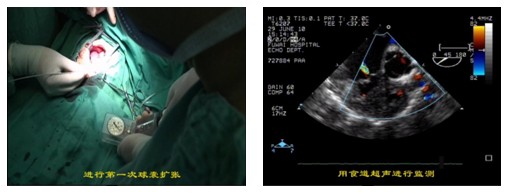

图注:胸部小切口下房间隔缺损\室间隔缺损封堵术

2.新生儿、小婴儿室间隔完整的肺动脉闭锁/重症肺动脉狭窄、此类患儿出生后早期即可出现严重缺氧紫绀、喂养困难、心功能衰竭,任其发展,相当一部分可在出生后1个月内死亡。如能及时解除梗阻不仅能改善患者缺氧症状, 还有利于促进肺动脉和右心室发育。与传统手术及经皮肺动脉瓣球囊扩张成形术相比较, 杂交手术(即经胸肺动脉瓣球囊扩张成形术)具有以下优点:(1) 防止外周血管损伤; (2) 避免体外循环所带来的损伤, 术后恢复快, 监护时间和气管内插管时间缩短; (3) 安全性较高, 扩张过程中如有组织撕裂出血、严重心律失常甚至心搏骤停或其他意外损伤, 可及时在直视下给与处理; (4) 对右心室、肺动脉发育较差患者可同期行体肺分流术, 有利于改善患者预后; (5)如扩张不满意, 合并右心室流出道梗阻时可同期转为体外循环下行右心室流出道疏通术, 避免二次手术。阜外医院资料显示,该技术围术期病死率、并发症发生率低; 中期随访肺动脉瓣再狭窄、肺动脉瓣反流发生率也较低, 大多数无需再干预即达到痊愈水平。因此, 经胸肺动脉瓣球囊扩张成形术是治疗新生儿及婴幼儿室间隔完整型肺动脉闭锁/重度肺动脉瓣狭窄安全有效的方法。

图注:新生儿、小婴儿室间隔完整的肺动脉闭锁/重症肺动脉瓣狭窄hybrid球囊扩张术,术中实时超声检测